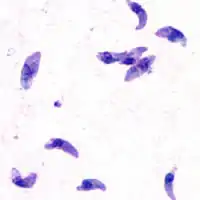

| Giemsa stained T. gondii tachyzoites, 1000× magnification | |

Tachyzoites

Motile, and quickly multiplying, tachyzoites are responsible for expanding the population of the parasite in the host.[44][27]: 19 When a host consumes a tissue cyst (containing bradyzoites) or an oocyst (containing sporozoites), the bradyzoites or sporozoites stage-convert into tachyzoites upon infecting the intestinal epithelium of the host.[27]: 359 During the initial acute period of infection, tachyzoites spread throughout the body via the blood stream.[27]: 39–40 During the later, latent (chronic) stages of infection, tachyzoites stage-convert to bradyzoites to form tissue cysts.